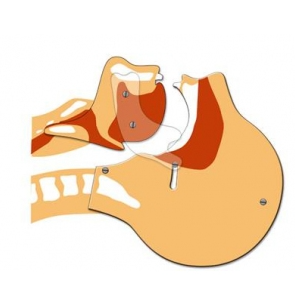

Modèle de tête articulée pour formations de secourisme

Outil pédagogique indispensable lors des formations de secourisme pour visualisation libération des voies aériennes.

La tête articulée représente une coupe de tête de profil.

Permet une schématisation précise des voies respiratoires.

Pour une formation efficace des gestes de secours à adopter pour la pratique de la respiration artifcielle.

– En plexiglas.

– Sans latex.

Dimensions de la plaque: largeur 24 x Hauteur 33 cm.

Dimensions de la tête: largeur 21,5 x Hauteur 31 cm.

Poids: 450 gr.

Garantie 1 an.